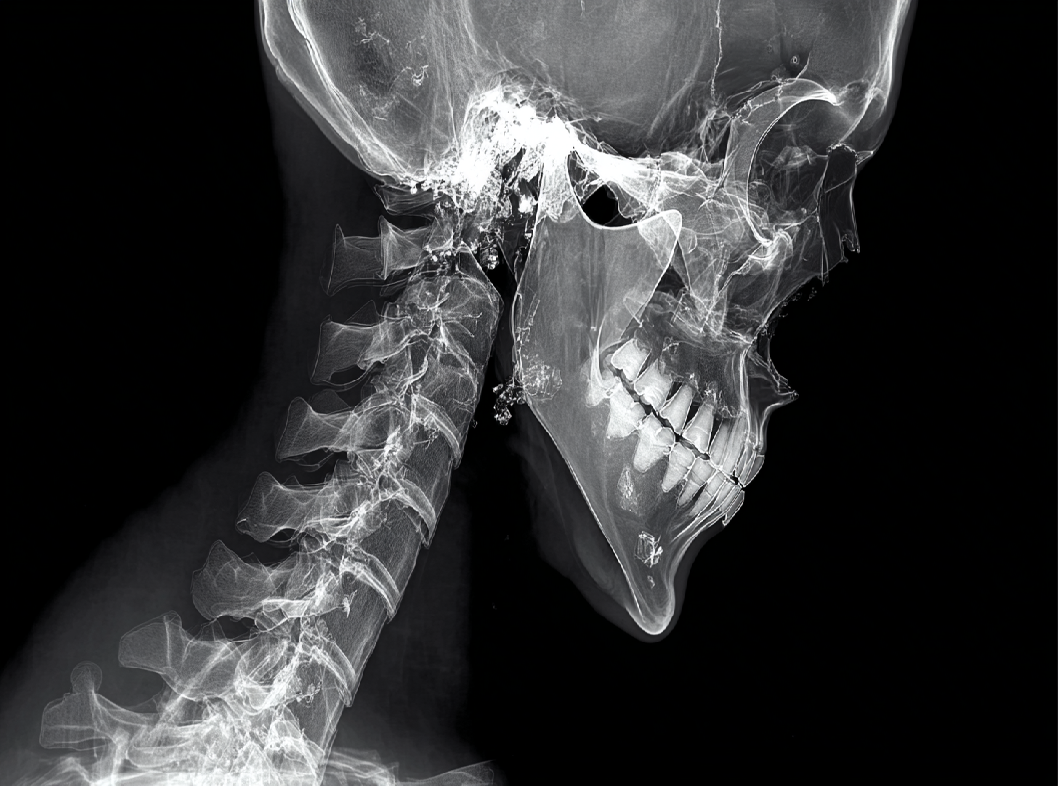

Диагностика ПА включает в себя клинический осмотр, рентгенографию и, в некоторых случаях, более сложные методы образования, такие как компьютерная томография или магнитно-резонансная томография. Лечение перелома атланта может варьироваться от консервативных методов, таких как ношение ортеза, до хирургического вмешательства для стабилизации позвоночника и восстановления его нормальной анатомии.